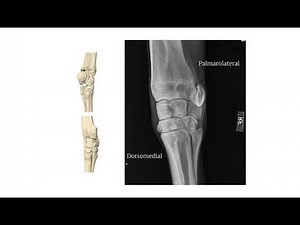

Radiology – DLPMO view intro

Obtaining the DMPLO (medial oblique) view of the hock

Obtaining the DLPMO (lateral oblique) view of the hock